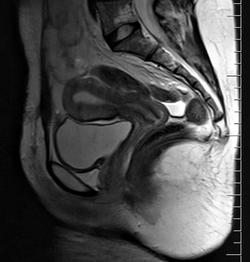

The female reproductive system is made up of the internal and external sex organs that function in the reproduction of new offspring. The human female reproductive system is immature at birth and develops to maturity at puberty to be able to produce gametes, and to carry a fetus to full term. The internal sex organs are the vagina, uterus, fallopian tubes, and ovaries. The female reproductive tract includes the vagina, uterus, and fallopian tubes and is prone to infections.[1] The vagina allows for sexual intercourse and childbirth, and is connected to the uterus at the cervix. The uterus or womb accommodates the embryo which develops into the fetus. The uterus also produces secretions which help the transit of sperm to the fallopian tubes, where sperm fertilize ova (egg cells) produced by the ovaries. The external sex organs are also known as the genitals and these are the organs of the vulva including the labia, clitoris, and vaginal opening.[2]

The uterus or womb is the major female reproductive organ. The uterus provides mechanical protection, nutritional support, and waste removal for the developing embryo (weeks 1 to 8) and fetus (from week 9 until the delivery). In addition, contractions in the muscular wall of the uterus are important in pushing out the fetus at the time of birth.

The uterus is a pear-shaped muscular organ. Its major function is to accept a fertilized ovum which becomes implanted into the endometrium, and derives nourishment from blood vessels which develop exclusively for this purpose. The fertilized ovum becomes an embryo, develops into a fetus and gestates until childbirth. If the egg does not embed in the wall of the uterus, a female begins menstruation.[4]

The fallopian tubes are two tubes leading from the ovaries into the uterus. On maturity of an ovum, the follicle and the ovary's wall rupture, allowing the ovum to escape and enter the fallopian tube. There it travels toward the uterus, pushed along by movements of cilia on the inner lining of the tubes. This trip takes hours or days. If the ovum is fertilized while in the fallopian tube, then it normally implants in the endometrium when it reaches the uterus, which signals the beginning of pregnancy.[5]